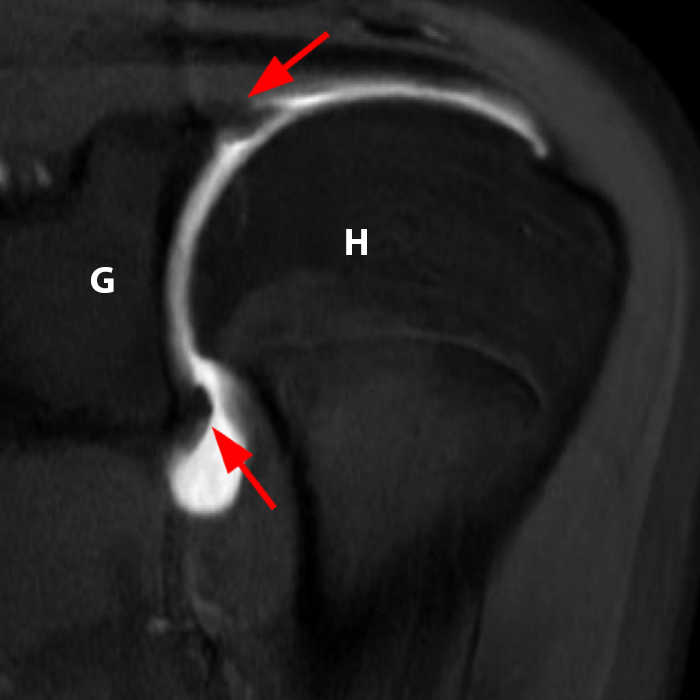

Labbro normale. Le immagini qui sopra MRA T1 FS coronali (sinistra) e assiali (destra) in un paziente di 24 anni mostrano un labbro normale (frecce). H: Testa omerale, G: Glenoide.